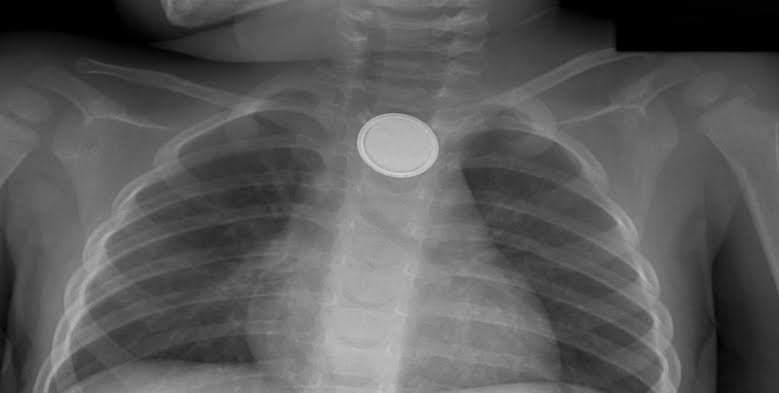

El Instituto Mexicano del Seguro Social (IMSS) Veracruz Sur hace un llamado a los padres de familia, para extremar precauciones y evitar que los niños especialmente menores de cinco años, manipulen todo tipo de pila y sea llevada a la boca, lo que podría causar severos daños en el esófago, incluso la muerte.

El director del Hospital General de Zona (HGZ) No. 36, doctor Omar Antonio García López explicó que la atención en urgencias a niños que mordieron o se tragaron una pila, es una de las principales causas de atención.

El esófago es el órgano más afectado por estos accidentes, cuando la pila permanece por mucho tiempo dentro se abre y puede liberar material tóxico que quema la mucosa, o bien liberar corriente eléctrica perforando la pared esofágica.

Las pilas de botón que se utilizan en relojes, lámparas, controles remotos, entre otros, son pequeñas y pueden ser ingeridas por los niños por curiosidad; en el caso de las pilas más grandes como la triple A y doble A, pueden ser mordidas, el líquido entra al interior en contacto con el infante, causando reacciones como vómito.